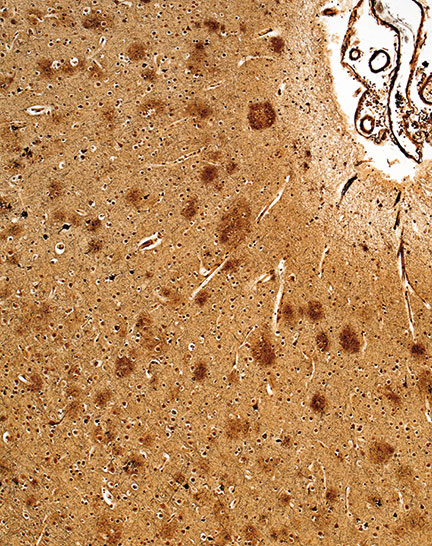

Thirty years later, the medical photographer and associate professor of pathology and art at the Johns Hopkins University’s School of Medicine will tell you that debilitating human diseases can actually be quite photogenic under the microscope, particularly when the professionals studying them use color stains to enhance different shapes and patterns.

“Beauty may be seen as the delicate lacework of cells within the normal human brain, reminiscent of a Jackson Pollock masterpiece, the vibrant colored chromosomes generated by spectral karyotyping that reminded one of our colleagues of the childhood game LITE-BRITE or the multitude of colors and textures formed by fungal organisms in a microbiology lab,” says Christine Iacobuzio-Donahue, a pathologist at the Johns Hopkins Hospital who diagnoses gastrointestinal diseases.

Barker and Iacobuzio-Donahue share in interest in how medical photography can take diseased tissue and render it otherworldly, abstract, vibrant and thought-provoking. Together, they collected nearly 100 images of human diseases and other ailments from more than 60 medical science professionals for Hidden Beauty, a book and accompanying exhibition. In each image, there is an underlying tension. The jarring moment, of course, is when viewers realize that the subject of the lovely image before them is something that can cause so much pain and distress.

Here is a selection from Hidden Beauty: